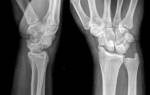

Рентгенография

Исследование с помощью рентгенографа проводят для оценки повреждения и уточнения наличия или отсутствия осложнений. В некоторых случаях вывих сопровождается образование трещины в головке кости, поэтому важно провести диагностику, чтобы правильно назначить лечение.

Исследование бесплатно проводится в государственных клиниках. На снимке врач видит степень повреждения и сопутствующие нарушения.

Лечение вывиха пальца, как правило, проводится консервативным способом. Врач под обезболиванием возвращает сместившуюся фалангу на анатомически правильное место. После этого выполняется контрольный снимок и, если манипуляция оказалась успешной, проводится фиксация пальца с помощью гипсовой повязки.